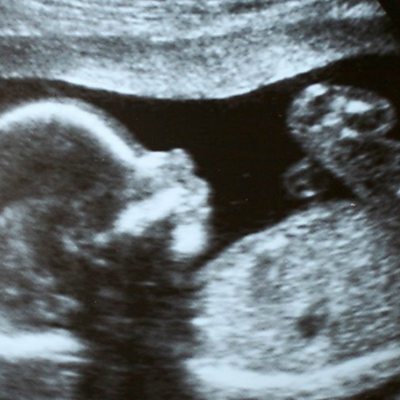

An inquiry into the ethical issues surrounding genetically altering a human embryo has said that editing human DNA could be ethically acceptable. Karen Yeung, professor of Law and Ethics at the University of Birmingham, is the chairwoman of the UK based Nuffield Council, the charity that did the research. Image: Sonogram image Credit: Getty Images.